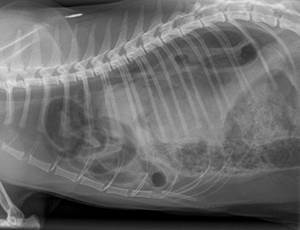

Диагностика диафрагмальной грыжи основывается на данных анамнеза (владелец описывает эпизод травмы), физикальном обследовании и рентгенографии грудной клетки. Типично исчезновение линии диафрагмы, затенение кардио силуэта, смещение легочных долей.

Органы брюшной полости (печень, петли кишечника) также визуализируются на снимке. При спорных случаях проводится контрастная рентгенография (кошке скармливают специальную суспензию, которая окрашивает петли кишечника).